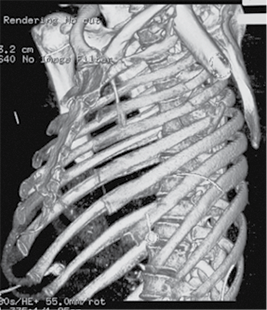

A 58-year-old patient was admitted to the Emergency Department of level I Trauma Center in August 2022 due to polytrauma sustained in a car accident. On arrival, the patient’s condition was severe, with decreased consciousness (GCS score of 12), unstable hemodynamic, subcompensated peripheral circulation, blood pressure of 62/32, and heart rate of 78 beats per minute. There was reduced breathing on the left side with a respiratory rate of 18 breaths per minute and an oxygen saturation (SpO2) of 85.0%. Palpation revealed pain in the left posterior chest. X-rays and CT scans were performed, which revealed a traumatic hemothorax on the left side, humeral head within the pleural cavity, three rib fractures, lung contusion, and hematoma.

Figure 1. First X-ray and computer tomography upon admission (with humeral head shown)

Figure 2. Subsequent 3D reconstruction